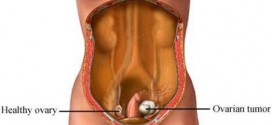

Leer MásARRENOBLASTOMA

El arrenoblastoma. Recordemos que la Trofología avanzada (binipatia), tiene el extraordinario poder de eliminación de las células cancerígenas (tumores), al igual que su maravillosa estrategia para detener el cáncer, al provocar la muerte de las células del cáncer por hambre. Esta es la maravillosa estrategia de la Trofología avanzada, hacer morir de hambre al cáncer mientras alimenta a las células …